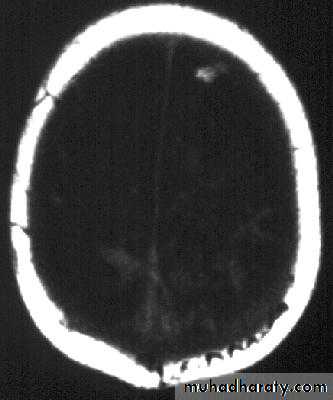

Subdural Empyemas

د.عبدالرحمن

• CT scanning;

Despite subdural empyema is a neurosurgical emergency, diagnosis is often delayed as the collection on CT is usually so slight and frequently missed.

2. MRI : useful when the diagnosis is doubtful.